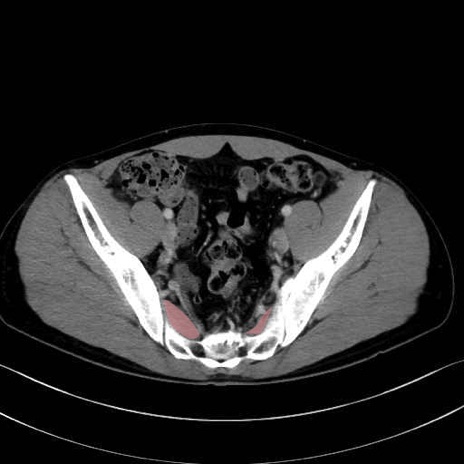

大腿方形筋 (Quadratus femoris)